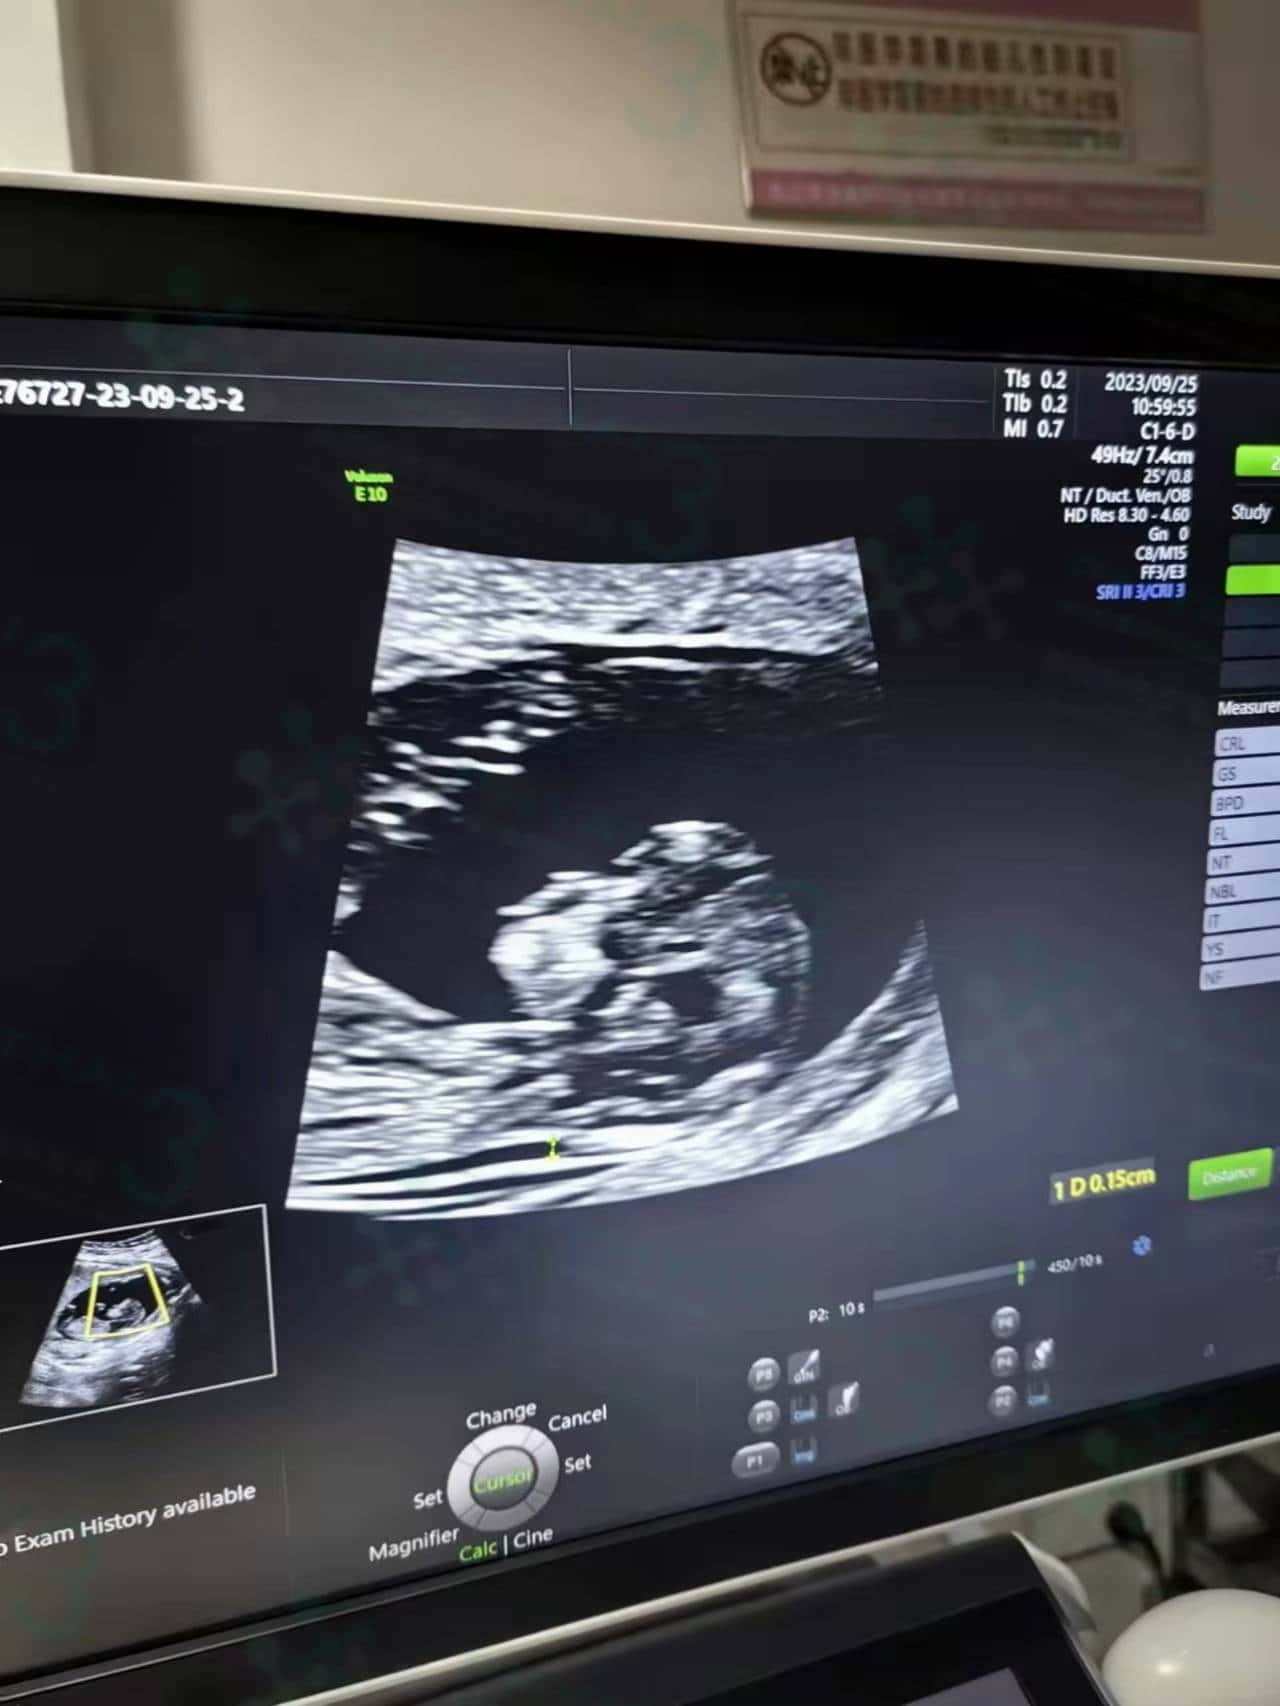

做试管跟自然怀孕,保胎的方式或做产检都是一样的,一般验孕成功之后患者就可以马上回国,后期在国内按照国内医生保胎和定时间做检查。正常情况怀孕6周查孕囊,8周查胎心胎芽,12周左右就可以开始做NT检查。

NT检查比普通B超细致很多,但有可能做检查的时候也会比较长,因为宝宝的每一个器官医生会仔细检查。今天宝宝很配合,医生截图拍照的时候就非常清晰。这被认为是第一次能清楚地看到宝宝的检查。看起来非常激动~希望后期孕妈妈们一切顺利,再等几个月,就能见到宝宝了。